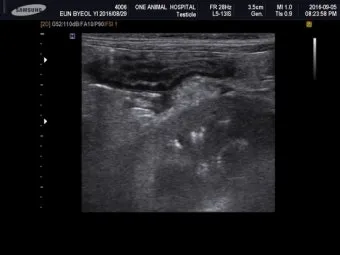

복부 초음파 검사 - 가장 기본적이면서도 중요한 1차 검사예요. 췌장의 크기나 모양 변화, 주변 장기와의 관계를 실시간으로 관찰할 수 있어요. 비용은 보통 15만원-25만원 정도이고, 검사 시간은 20-30분 정도 걸립니다.